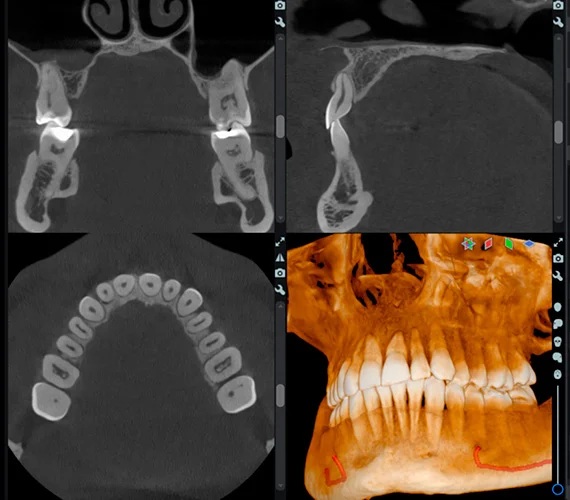

Zobrazení čelistního kloubu (TMJ) - Bolesti temporomandibulárního kloubu (TMJ) postihují významnou část populace. Software Romexis nabízí speciálně navržené náhledy pro vyšetření a analýzu problémů s tímto kloubem. Oba klouby pacienta lze v softwaru vyhodnotit současně a provádět přesná měření. Díky umělé inteligenci Romexis automaticky rozpozná kondyly.

Efektivní analýza dýchacích cest - Segmentace dýchacích cest v softwaru Romexis probíhá pomocí několika jednoduchých kliknutí. Software automaticky vypočítá jejich objem a minimální plochu a vizualizuje dýchací cesty pacienta pomocí výrazných barev. Náš zobrazovací protokol Planmeca Ultra Low Dose™ pro CBCT je zároveň ideální volbou pro vyšetření dýchacích cest, protože výrazně snižuje dávku záření bez statisticky významného snížení kvality diagnostického obrazu.